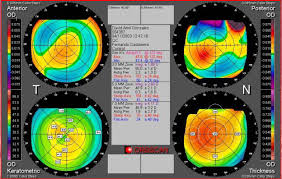

Es mas, la tecnología de la que disponemos ,TOPOGRAFOS de ultima generación ,que nos dan información del astigmatismo de cara anterior y posterior de nuestra cornea y OCT anterior (tomografía de coherencia óptica), que permite, mediante un haz de láser infrarrojo, obtener una imagen microscópica y en tres dimensiones de la córnea. Gracias “podemos ver cómo la lente de contacto se apoya en cada punto de la córnea de forma objetiva y, por tanto, diseñarla absolutamente a medida”, nos facilita en todo momento las adaptaciones complicadas y no tan complicadas.